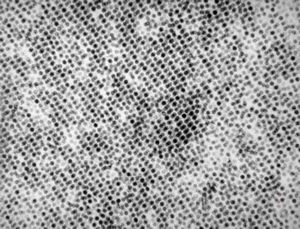

adenovirus in tissue culture - paracrystalline formation